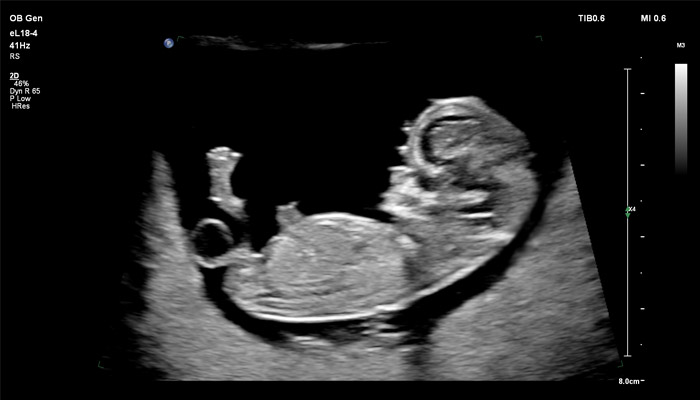

Детальная анатомия плода и ранняя диагностика пороков в I триместре

Линейный матричный датчик eL18-4 позволяет получить детальную информацию об анатомии плода и выявить пороки на ранней стадии развития. Сверхширокополосная PureWave матрица датчика генерирует частоты в диапазоне 2-22 МГц, что формирует одинаково высокоинформативные, четкие изображения по всей глубине сканирования до 14 см.

Высокочастотный датчик Philips eL18-4 содержит решетку из 1920 активных монокристаллических пьезоэлементов, выполненных по усовершенствованной технологии PureWave. Это обеспечивает высокодетальную 2D визуализацию, которая в совокупности с глубиной сканирования необходима для уверенной диагностики в акушерстве.

До введения высокочастотных линейных датчиков точная ультразвуковая диагностика мочевой системы плода была доступна в основном после 16-17 недель беременности. Новая технология еL18-4 позволяет проводить раннюю морфологическую оценку плода уже в первом триместре. Клинический случай с применением eL18-4 демонстрирует, что кортико-медуллярная дифференцировка почек плода возможна на 14 неделе беременности”.

Использование линейного матричного датчика eL18-4 при осмотре беременных в I триместре, особенно на ранних сроках, позволяет ограничиться трансабдоминальным сканированием вместо трансвагинального и при этом получить максимально полную диагностическую информацию. Отсутствие полостного исследования чрезвычайно важно для соблюдения принципа ALARA – использования минимальной необходимой мощности для безопасности пациента. Благодаря применению мультичастотного датчика с диапазоном от 2 до 22 МГц через переднюю брюшную стенку хорошо определяется эмбрион длиной 3 мм, что соответствует шестой неделе беременности. В конце I триместра с eL18-4 достаточно отчётливо визуализируется четырёхкамерный срез сердца, мочевой пузырь и сосуды пуповины, которые, как правило, определяются только при трансвагинальном сканировании.

Во II триместре беременности высокая разрешающая способность eL18-4 позволяет детально изучить структуру органов и тканей и увидеть многие нюансы, которые при работе другими датчиками не обнаруживались или становились очевидны в более поздние сроки. Например, у 19-недельного плода визуализируется перегородка носа, мышцы языка, диафрагма между грудной и брюшной полостью, на 20-й неделе чётко определяются оболочки спинного мозга и уретра, а на 24-й – хорошо дифференцируются корень лёгкого, борозды и извилины мозжечка и многие другие структуры.